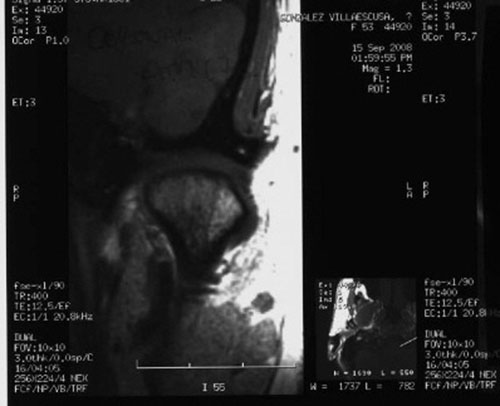

RMN de ATMs (17-09-2008): Dentro de la normalidad.

– ATMs dentro de la normalidad.

PRUEBAS DIAGNOSTICAS COMPLEMENTARIAS:

REF. 2